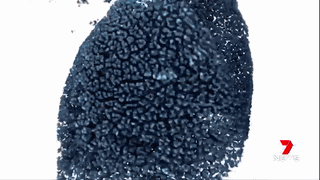

澳洲的科學(xué)家們通過(guò)運(yùn)用納米技術(shù),將“基因沉默”(gene silencing)藥物運(yùn)送至腫瘤細(xì)胞中來(lái)治療胰腺癌。

藥物已經(jīng)在擁有和人類相仿的瘢痕組織的小鼠身上進(jìn)行試驗(yàn),并獲得成功。